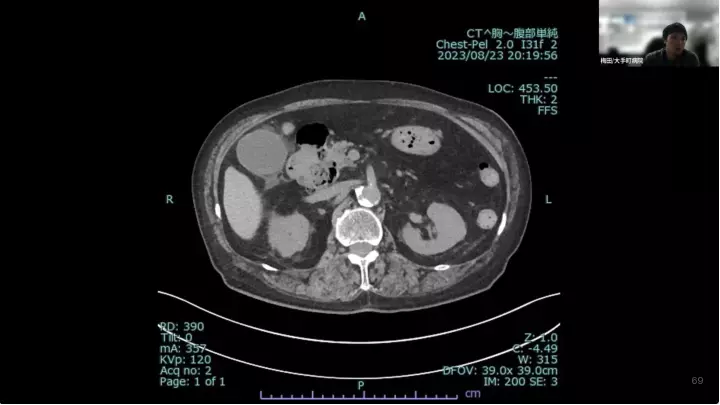

外科医目線の~急性胆嚢炎~治療編